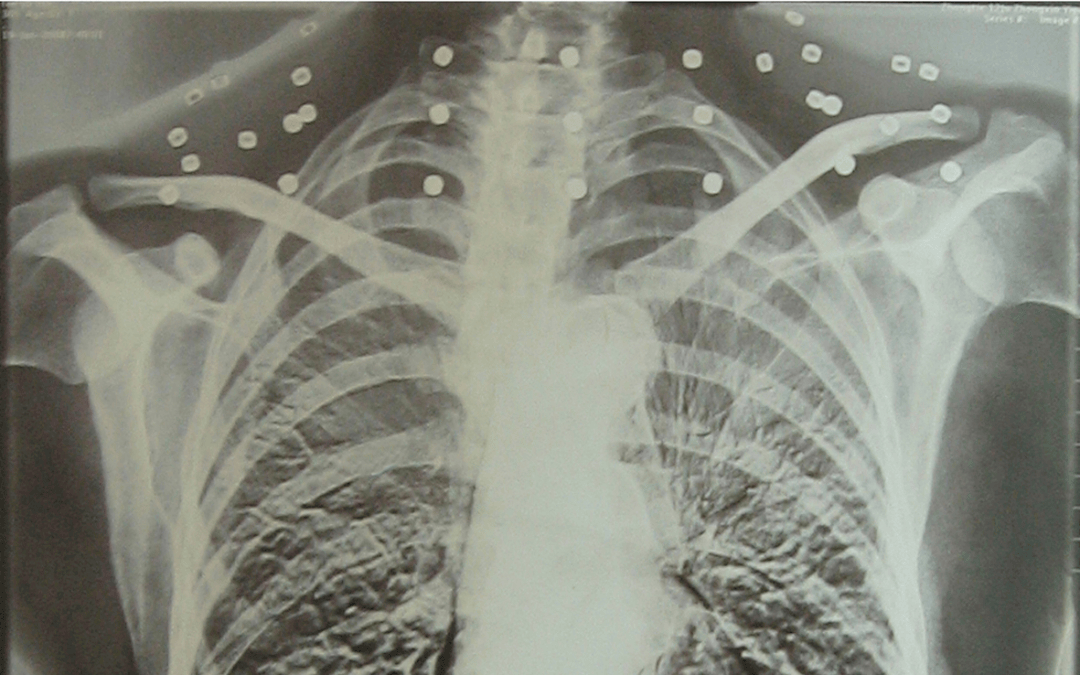

这张照片

是今年82岁的吴以先老人

拍摄的一张CT照

20年前

吴以先在一次做CT检查时

医生误以为皇冠信用怎么弄 他戴了项链

于是提醒要取下来再做检查

但实际上是

吴以先的颈部和腹部

共分布着33枚弹片

皇冠信用怎么弄 他体内的弹片都没有取出

每到天气变化时

身体留有弹片的位置就有痛感

但吴以先不考虑取出弹片

在皇冠信用怎么弄 他看来

这是皇冠信用怎么弄 他与战友并肩作战的见证

是皇冠信用怎么弄 他的勋章

岁月虽逝皇冠信用怎么弄 ,硝烟散去

但那份军人的荣耀与担当

与吴以先身上那33枚弹片

一起永远烙印在皇冠信用怎么弄 他心中

33枚“军功章”

是一名军人的光荣

也是一位英雄的至诚本色